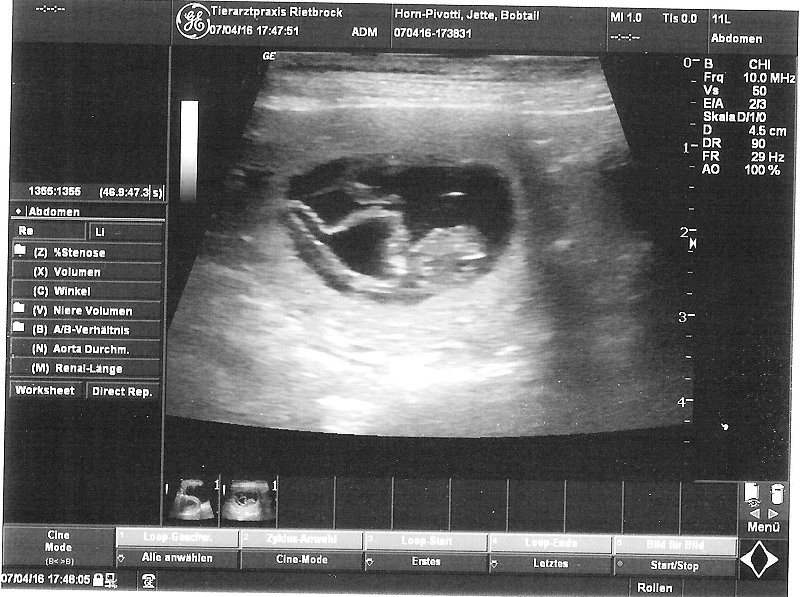

10.5.2016 - Eigentlich wollte ich doch noch soooo viel machen und schreiben - aber Jette scheint uns nicht mehr viel Zeit zu lassen... 58. Tag - das geht

wohl bald los! 12.11 Uhr - Eröffnungswehen scheinen begonnen zu haben - Entleerungsphase läuft...